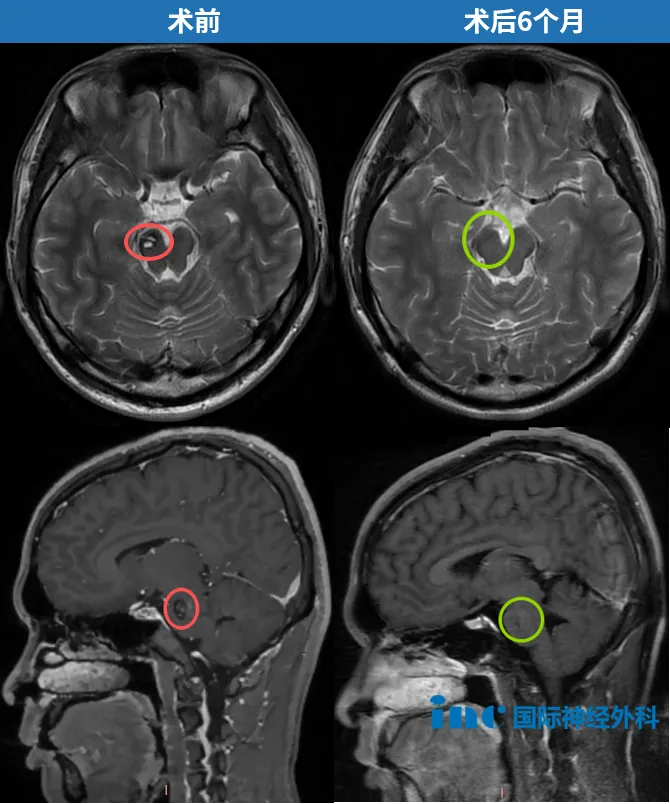

吴先生的病灶位于大脑脚中脑腹侧面,毗邻脚间窝。这处位置深藏于大脑核心,手术入路通道极为狭窄,周围密集排布着负责控制对侧肢体运动的神经纤维。一旦操作失当,轻则引发偏瘫,重则全身瘫痪。动眼神经同样穿行于此——手术中的任何闪失,都可能造成瞳孔散大、复视或眼睑下垂,而且这些损伤很可能是终身性的。

术后一个月复查:教授说,"不能更好"

巴教授仔细审阅了术后核磁共振影像后说道:"这是一份非常漂亮的复查结果。桥脑内仅有极少量局部瘢痕形成,含铁血黄素沉积量也比其他患者术后的影像低得多。实际上,不能更好了。"